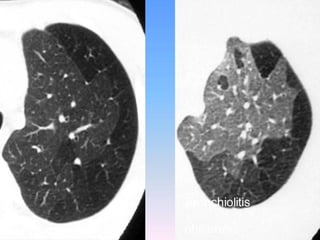

Common CT findings include bronchial wall

thickening, air trapping, and bronchiectasis.

Importantly, CT imaging might be necessary to

rule out diseases that masquerade as asthma,

such as intrathoracic or extrathoracic airway

obstruction, obliterative bronchiolitis, chronic

obstructive pulmonary disease, congestive heart

failure, hypersensitivity pneumonitis,

hypereosinophilic syndromes, allergic

bronchopulmonary aspergillosis, and eosinophilic

granulomatosis with polyangiitis (Churg-Strauss

syndrome).